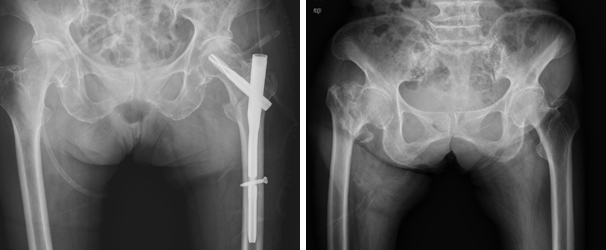

압박 고나사 고정술 압박 고나사 고정술 이미지

골수강내 고정술 골수강내 고정술 이미지

인공관절 반치환술 인공관절 반치환술 이미지